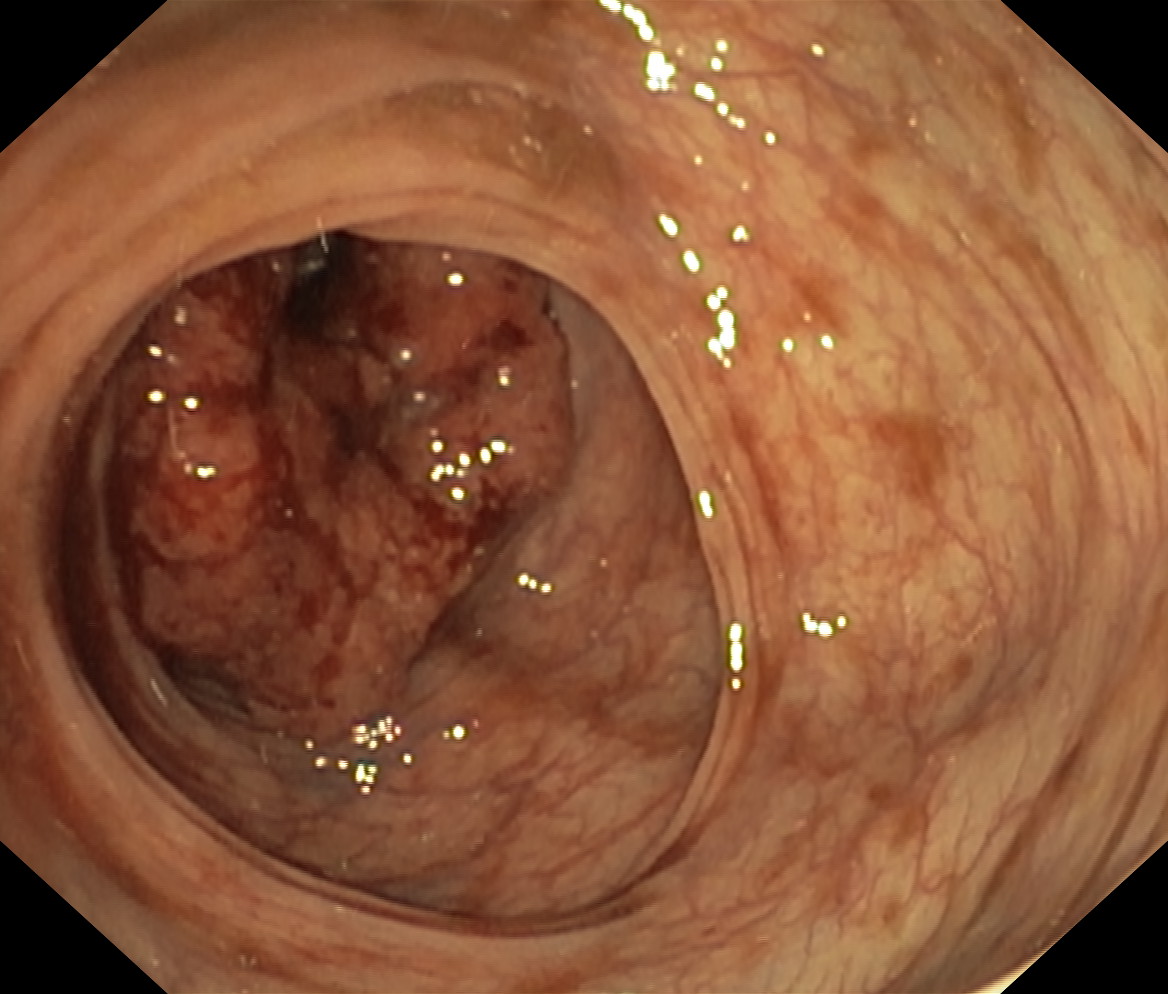

Nowotwory przewodu pokarmowego